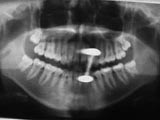

Wird nichts mehr empfunden so ist er tot und das tote Gewebe muss schnellstens aus dem Zahn entfernt werden (Wurzelkanalreinigung) bevor es im Zahn verfault und zu starken Schmerzen bis hin zur dicken Backe (Zyste) führt. Obwohl im Bild zur Verdeutlichung dargestellt ist eine Aufbereitung des Wurzelkanals (Nervnadel ragt über Wurzel hinaus ) über die Wurzel in den Kieferknochen bei der Zahnwurzelbehandlung natürlich nicht erwünscht. Um dies zu vermeiden müssen während der Wurzelbehandlung Röntgenaufnahmen angefertigt werden, die die ungefähre Länge der Wurzel berechnen lassen. Besser noch lässt sich die Länge der Wurzel elektronisch bestimmen .(Auf Wunsch Privatleistung). Ist die Wurzel an Ihrem Ende weit geöffnet kann es trotz aller Vorsicht zu einem ungewünschten Überaufbereiten und zu einer Überfüllung der Wurzel kommen. Dies beeinträchtigt dann oft den Erfolg. html Text zum Ausdrucken als pdf Datei. Falls über die Wurzelspitze hinaus in den umliegenden Knochen bereits Eiter aufgetreten ist und dieser den Knochen um den Zahn auflöst (das sieht man im Röntgenbild), so muss die infektiöse Wurzelspitze und die darum liegende Zyste entfernt werden .Im Prinzip ähnlich einem Pickel ausdrücken. Sobald der Druck (Eiter) dann heraus kann, geht sehr schnell der Schmerz bzw. auch die dicke Backe zurück. Der Vorgang nennt sich Wurzelresektion oder Apektomie. Die moderne Wurzelbehandlung umfasst Nickel-Titan-Feilen mit drehmomentregulierten Motoren gegen Instrumentenbruch, elektronische Längenmessung, Langzeit-provisorische Wurzelfüllungen mit provisorischen Langzeit-Füllungen. Alles leider Dinge die nicht in der Kassenleistung enthalten sind. So bleiben für den Patienten Kosten von ca. 60-480 EUR (je nach Schwierigkeit ) pro Kanal Aus manchen spezialisierten Prominentenpraxen wurde mir schon von Preisen bis zu 1200 EUR pro Kanal berichtet.